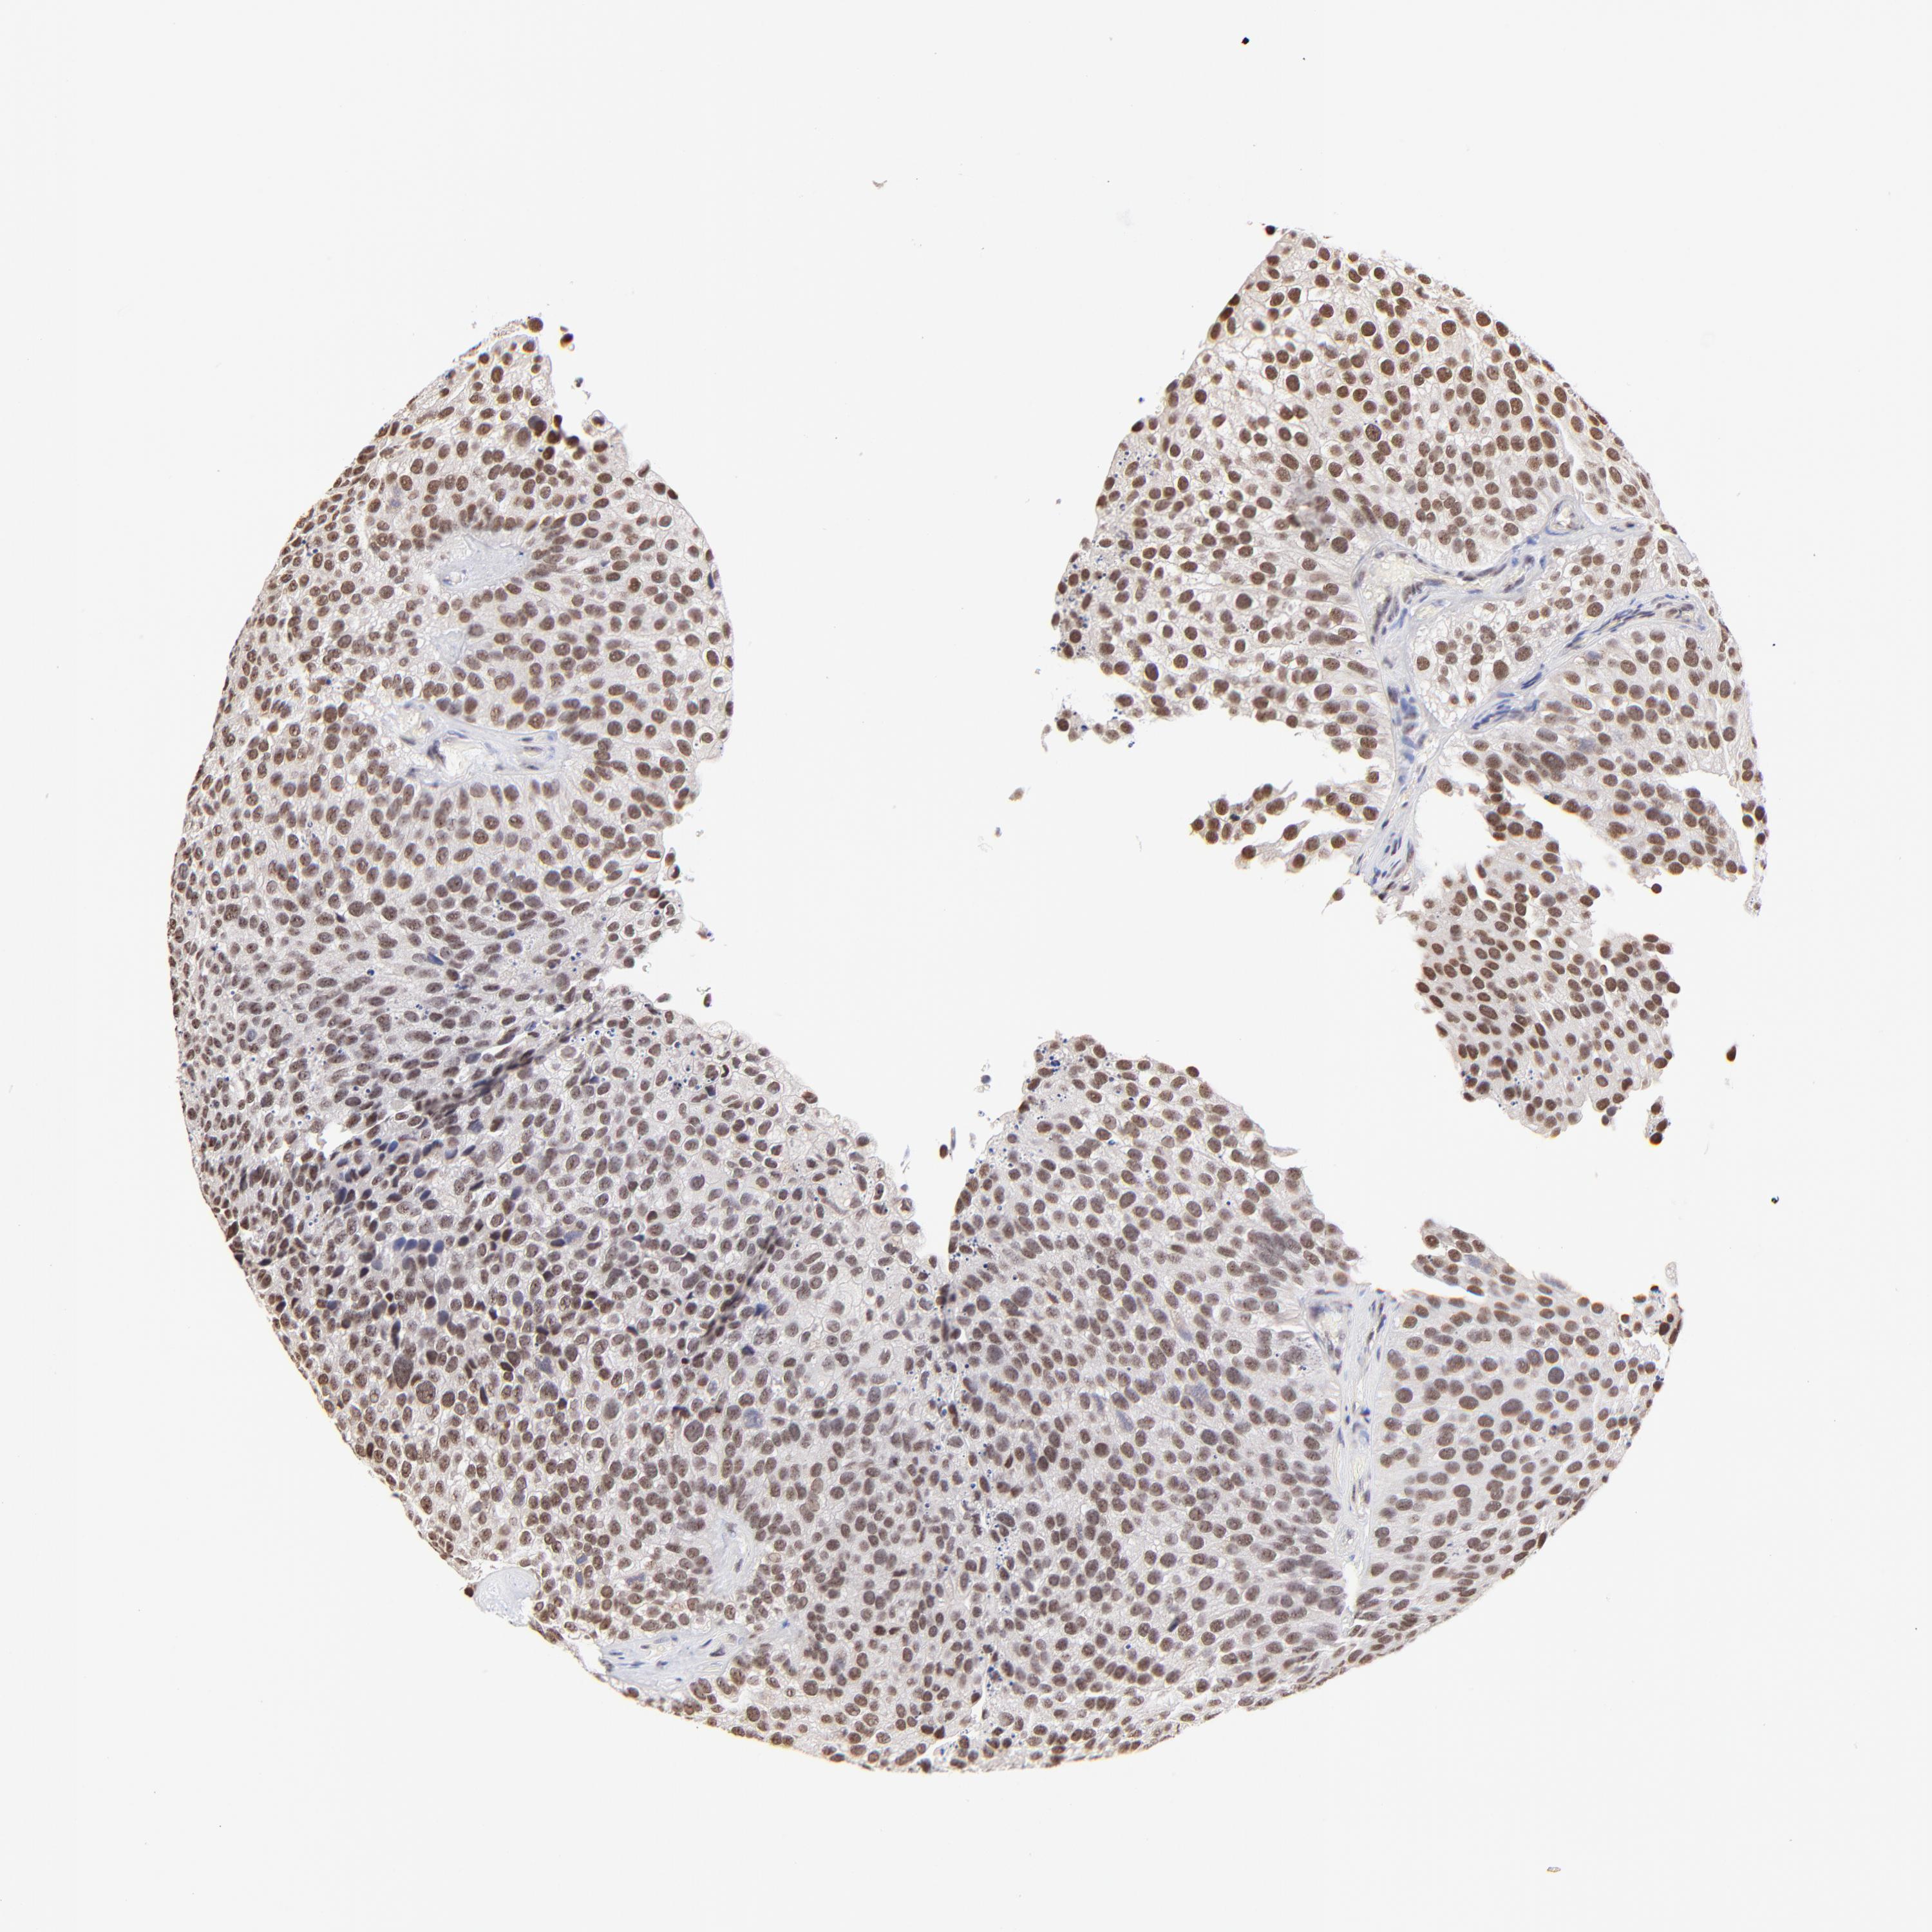

UROTHELIAL CANCER - Protein expressioni

A mouse-over function shows sample information and annotation data. Click on an image to view it in a full screen mode. Samples can be filtered based on level of antibody staining by selecting one or several of the following categories: high, medium, low and not detected. The assay and annotation is described here.

Note that samples used for immunohistochemistry by the Human Protein Atlas do not correspond to samples in the TCGA dataset.

Antibody stainingi

Antibody staining in the annotated cell types in the current human tissue is reported as not detected, low, medium, or high, based on conventional immunohistochemistry profiling in selected tissues. This score is based on the combination of the staining intensity and fraction of stained cells.

Each image is clickable and will lead to virtual microscopy that enables deeper exploration of all samples and also displays staining intensity scores, fraction scores and subcellular localization as well as patient and tissue information for each sample.

Antibody HPA003142

Staining

High

Medium

Low

Not detected

Intensity

Strong

Moderate

Weak

Negative

Quantity

>75%

75%-25%

<25%

None

Location

Nuclear

Cytoplasmic/membranous

Cytoplasmic/membranous,nuclear

Urothelial carcinoma, High grade

Urothelial carcinoma, Low grade

Adenocarcinoma, NOS